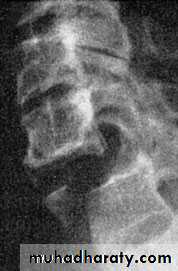

Burst and compression-flexion (‘teardrop’) fractures

These severe injuries are due to axial compression ofthe cervical spine,

usually in diving or athletic accidents

If the vertebral body is crushed in

neutral position of the neck the result is a ‘burst

fracture’. With combined axial compression and flexion,

an antero-inferior fragment of the vertebral body

is sheared off, producing the eponymous ‘tear-drop’

on the lateral x-ray. In both types of fracture there is a

risk of posterior displacement of the vertebral body

fragment and spinal cord injury.

diagnosis

Plain x-rays show either a crushed vertebral body(burst fracture) or a flexion deformity with a triangular fragment separated from the antero-inferior edge of the fractured vertebra (the innocent-looking ‘teardrop’).

CT or MRI should be performed

to look for retropulsion of bone fragments

into the spinal canal.